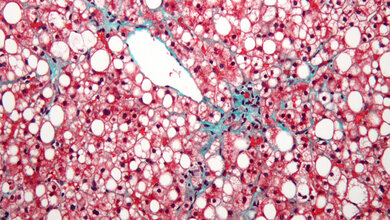

Viele Patienten, die an Leberzirrhose leiden, sterben an unbehandelbaren bakteriellen Infektionen. Ein Forscherteam der Uni Bonn und der TU München hat nun herausgefunden, dass durch in die zirrhotische Leber einwandernde Darmbakterien für die Infektabwehr zuständige Immunzellen abgeschaltet werden.

Pro Jahr sterben in Europa rund 170.000 Menschen an den Komplikationen einer Leberzirrhose. Häufige Ursachen der weit verbreiteten Erkrankung sind Alkoholmissbrauch, Fettleberhepatitis und chronische Virushepatitis. Leberzirrhosen entwickeln sich schleichend im Lauf von Jahren und Jahrzehnten. Dabei gehen Leberzellen zugrunde, die durch Bindegewebe ersetzt werden und damit die Durchblutung der Leber beeinträchtigen. Dies führt zu einem erhöhten Druck in den Blutgefäßen des Darms und damit zu einem Auswandern von Darmbakterien, die somit über das Blut die Leber erreichen.

An Mäusen, die an einer Leberzirrhose litten, haben die Forscher beobachtet, dass für die Infektabwehr zuständige Immunzellen, nämlich Makrophagen und Monozyten in der Leber, in Antwort auf unschädliche Darmbakterien anhaltend Typ-1-Interferon produzierten. Wurden diese Immunzellen dann von einer geringen Zahl von krankmachenden Listerien infiziert, wurde die Typ-1-Interferon-Produktion massiv angekurbelt. In der Folge kam es zur Ausschüttung von immunregulierendem Interleukin-10, was zum Zusammenbruch der Abwehrfunktion der Makrophagen gegen bakterielle Infektionen und damit zum tödlichen Ausgang von Infektionen führte.